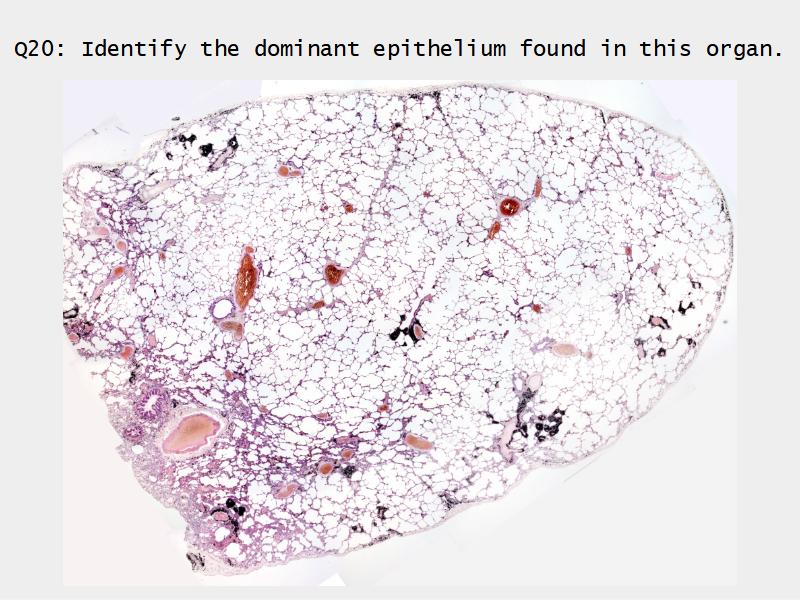

Slides: Respiratory System

- Slide 72 & 74: Lung

Lungs